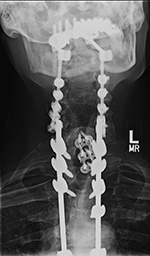

| Occiput-T8 posterior fusion with anterior cervical fusion from C6-T1. |

| 59 year-old man with occiput to T8 posterior fusion. There is anterior cervical fusion from C6-T1. PEEK disk cages are present at C6-7 and C7-T1. An old compression fracture is present at T5. In the cervical spine lateral mass screws are at C3-6 bilaterally. In the thoracic spine pedicle screws are at T1-3 and T6-8 on the right and at T1-4 and T6-8 on the left. Laminectomies have been performed from C3 to C6. |